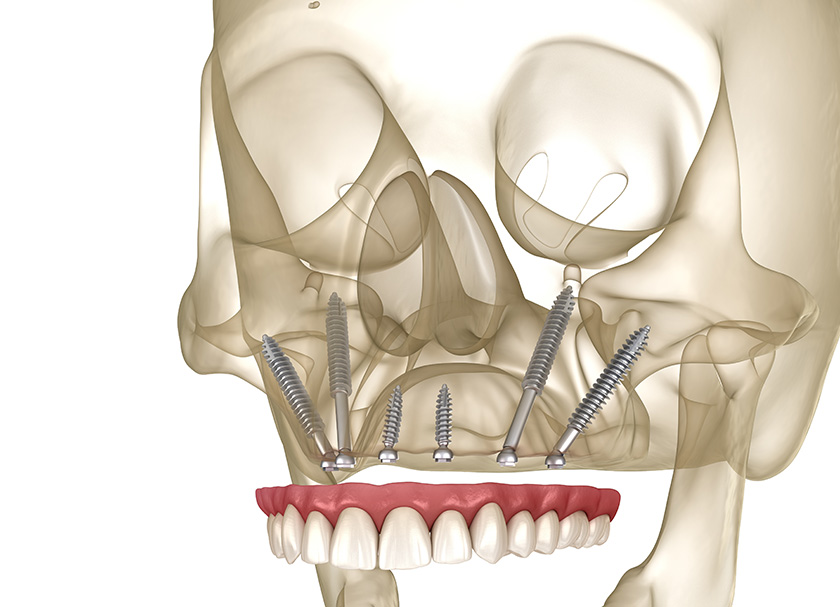

Basal bones are also called cortical implants because these implants are fitted into the cortical bone. The cortical bone is found in almost everybody despite acute bone loss due to gum disease or lack of teeth.

The basal bone is the strongest in the jaw and is formed even before the development of the teeth. Utilizing this bone as a support is an extremely strong way of placing the implant.

The number of dental implants is determined based on the amount and quality of the bone present. After providing anesthesia, the implants are placed in the thick cortical bone. They are then secured intact.

The impression of your jaw and the implants are taken digitally, and a prosthesis is fabricated. It is locked with basal implants with the help of screws and adjusted to give you a natural feel.